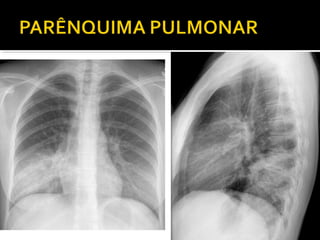

Este documento fornece parâmetros técnicos para realizar uma radiografia de tórax, incluindo posicionamento correto do paciente, dose adequada de radiação e estruturas anatômicas a serem avaliadas, como coração, pulmões, pleura, diafragma e ossos do tórax.